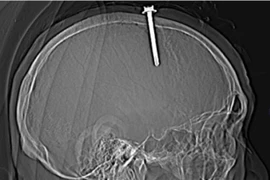

Người đàn ông tự đóng cây đinh dài 5 cm vào đầu mình

(Vietnamdaily) - Do khó ngủ, cảm thấy đau đớn trong người rồi sinh ra trầm cảm, một người đàn ông ở Thanh Hóa đã lấy một cây đinh dài 5 cm tự đóng vào đầu mình.